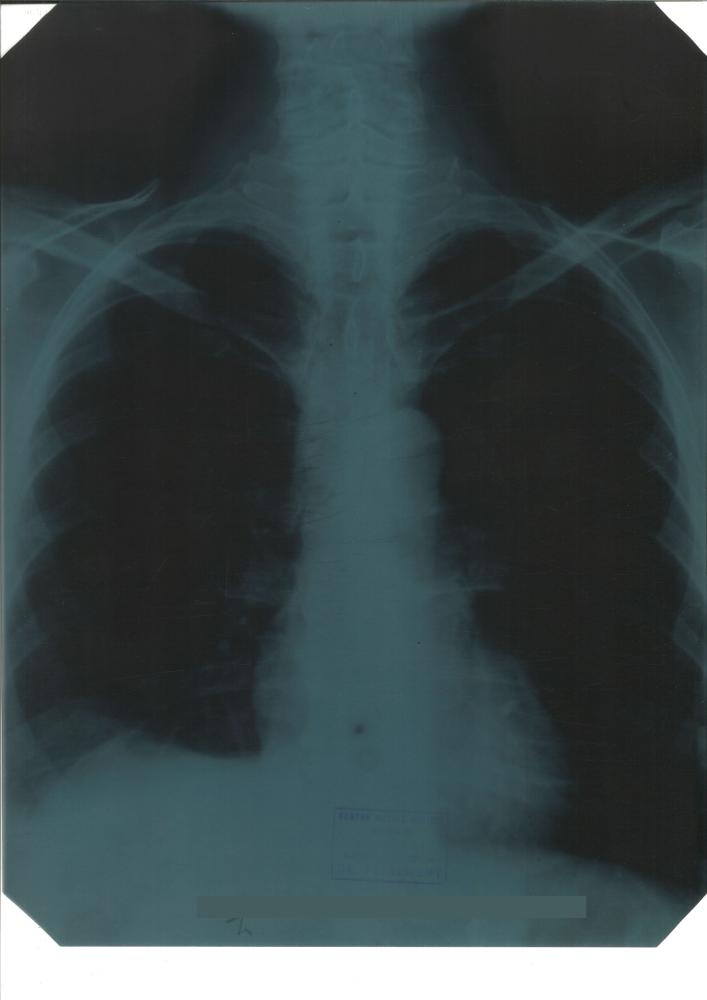

Los fondos documentales fueron donados por su hijo Rafael Vara Thorbeck e ingresaron en el Archivo el 12 de mayo de 2000. Están formados por historias clínicas y fichas de diagnósticos y tratamientos de pacientes entre 1927 y 1977, atendidos en el Hospital Provincial de Burgos, La Clínica del Dr. Vara y la Clínica de San Francisco de Asís de Madrid, documentación económica y de administración de las clínicas, correspondencia profesional y personal y documentación relacionada con su actividad docente: discursos, conferencias, curricula de alumnos, diapositivas, etc. y algunas fotografías.